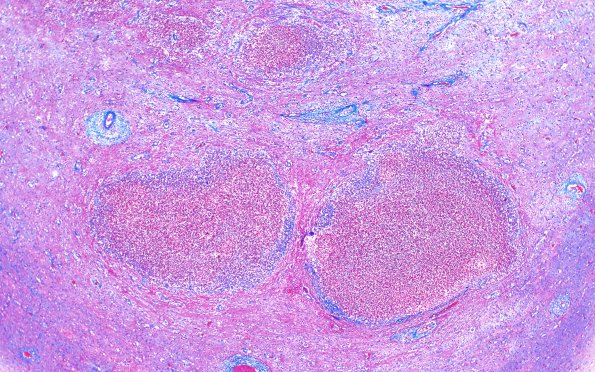

Washington University Experience | INFECTION | Bacteria | Abscess | Abscess, Subacute - Chronic | 17F5 Abscess B (Case 17) N12 TRI 20X

17F5,6 The small abscesses of image initially shown as image #16C9 demonstrate a thin collagenous capsule. (Trichrome)